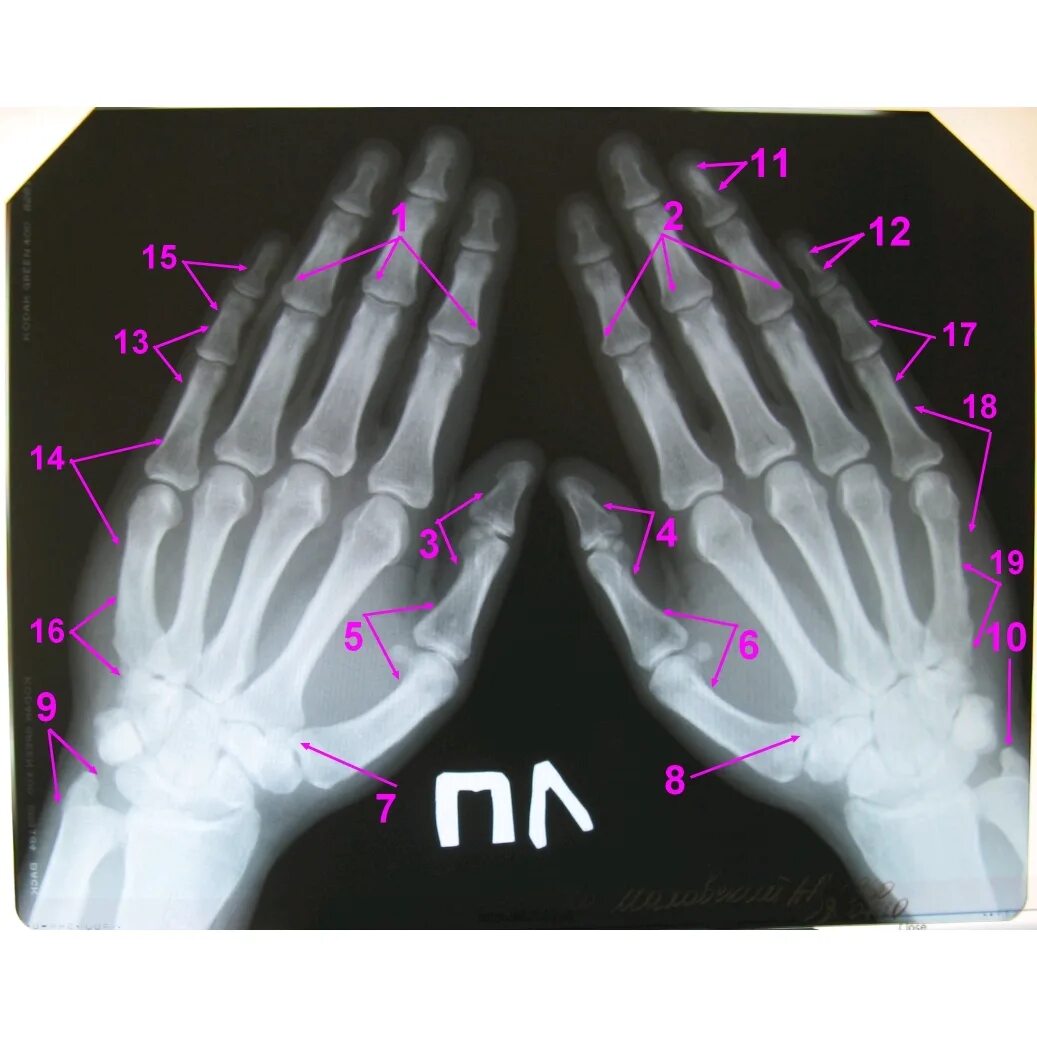

Поражение пястно фаланговых и проксимальных межфаланговых суставов